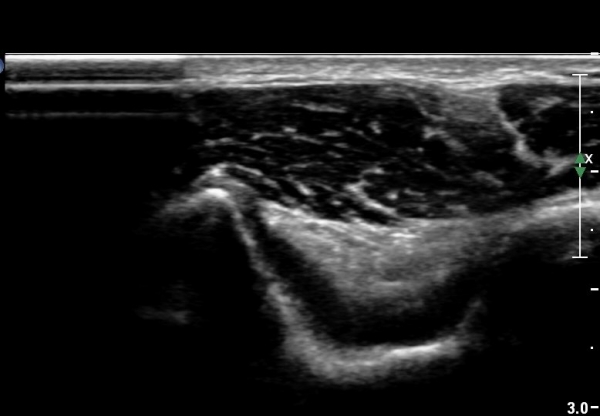

Á¶±Ý ´õ ¿ÜÃøÀ¸·Î À̵¿ÇÏ¿© °üÂûÇÏ´Ï °Ç°ú ÀδëÀÇ ÆÄ¿­ÀÌ ¶Ñ·ÈÇÏ´Ù(»çÁø 4, 5).